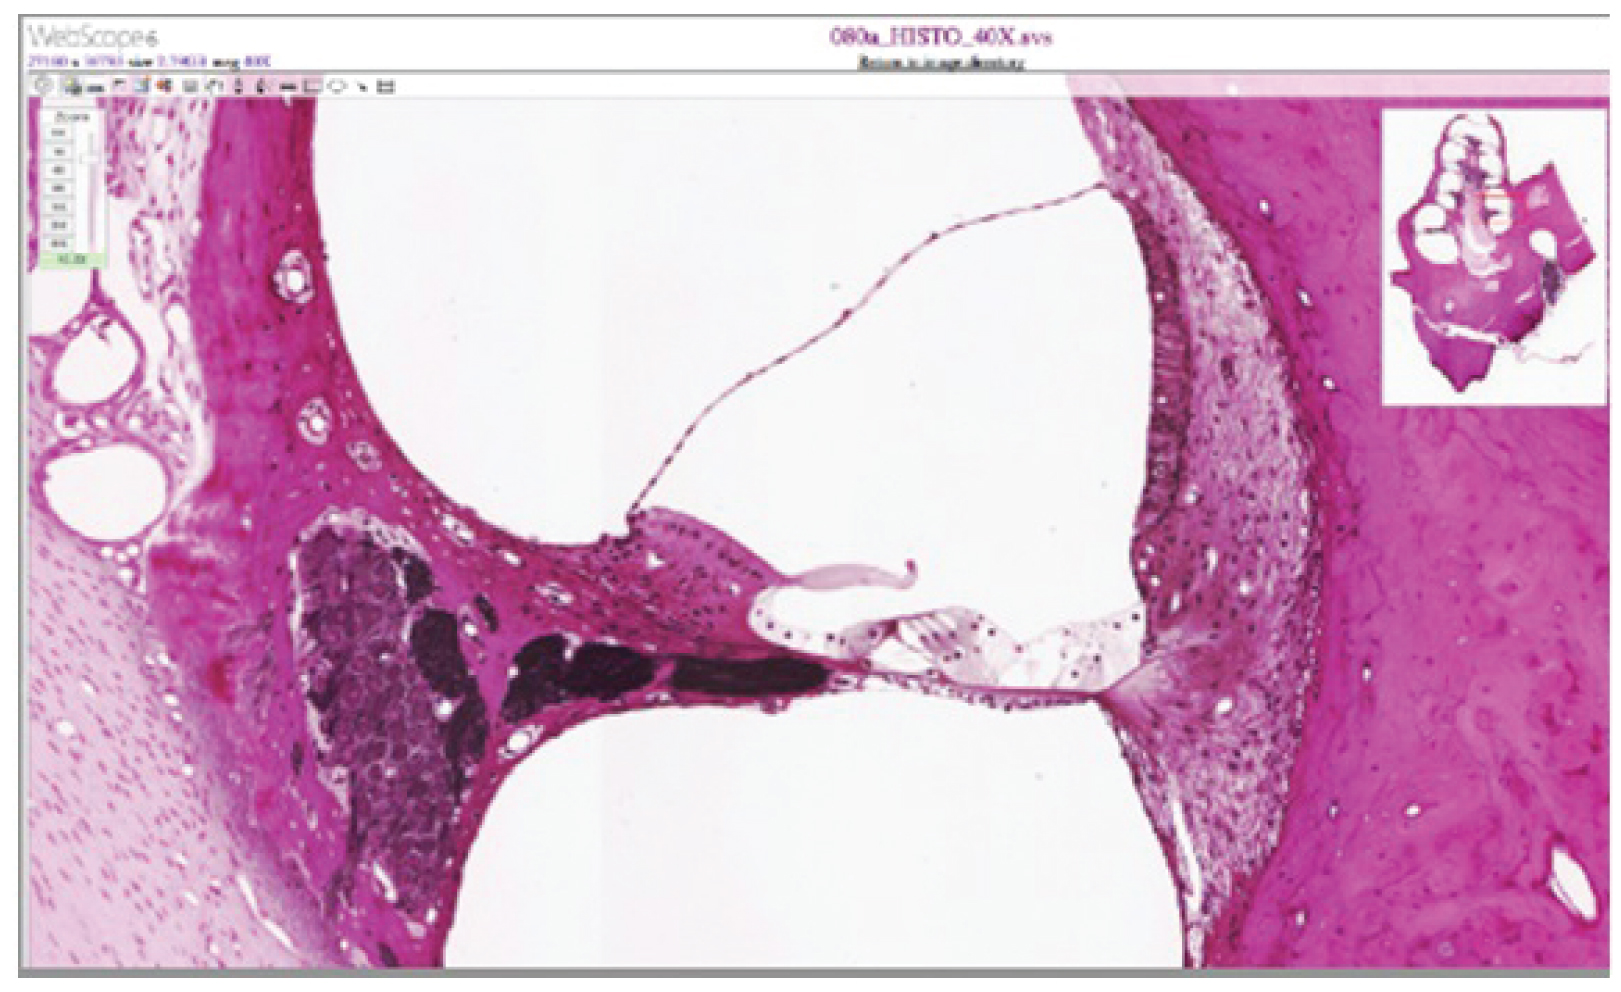

View the University of Michigan WebScope at http://virtualslides.med.umich.edu/Histology/Central%20Nervous%20System/080a_HISTO_40X.svs/view.apml to explore the tissue sample in greater detail. The basilar membrane is the thin membrane that extends from the central core of the cochlea to the edge. What is anchored to this membrane so that they can be activated by movement of the fluids within the cochlea?

[link] The basilar membrane is the thin membrane that extends from the central core of the cochlea to the edge. What is anchored to this membrane so that they can be activated by movement of the fluids within the cochlea?

[link] The hair cells are located in the organ of Corti, which is located on the basilar membrane. The stereocilia of those cells would normally be attached to the tectorial membrane (though they are detached in the micrograph because of processing of the tissue).